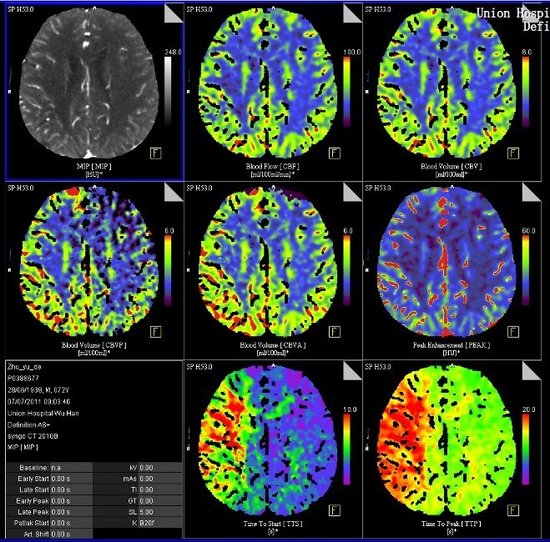

头颅CT灌注成像

脑灌注成像是在静脉快速灌注对比剂时,对感兴趣区层面进行连续CT扫描,从而获得感兴趣区时间—密度曲线,并利用不同的数学模型,计算出各种灌注参数值,因此能更有效、并量化反映局部组织血管灌注的改变,对明确病灶的血液供应具有重要意义,为急性脑缺血病灶发现、功能评价/肿瘤良恶性诊断、分期分级的神器。